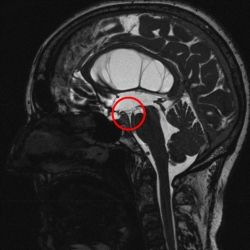

Prinzipiell stehen bei noch offener Fontanelle die Sonographie und die Kernspintomographie (MRT) zur Verfügung. Die Sonographie hat meist eine zu geringe Auflösung um zur Ursachendiagnostik eingesetzt zu werden. Die Computertomographie ist zur Ursachendiagnostik nicht sinnvoll, da der Informationsgehalt zu gering und die Strahlenbelastung für das kindliche Gehirn problematisch ist und vermieden werden soll. Somit ist die MRT die Untersuchung der Wahl. Da die diagnostische Präzision des MRT im Wesentlichen von der Qualität der Untersuchung abhängt, führen wir eine speziell auf die HIrnwasserräume abgestimmte hochauflösende Kernspintomographie, ggf. in Narkose, durch. Die Qualität dieser Aufnahmen unterscheidet sich erheblich von einer sog. „Standard-Kernspintomographie“. Mit diesem Vorgehen gelingt es häufig, zumindest eine erkennbare Ursache für einen Hydrocephalus darzustellen.

Das hierfür verwendete Verfahren ist die endoskopische Ventrikulozisternostomie (englisch endoscopic third ventriculostomy = ETV). Hierbei wird ein feines Endoskop in die erweiterten Hirnkammern vorgeschoben und damit am Boden des 3. Ventrikels in einem Areal, welches keine Funktion enthält, unter Sicht meist mit einem Speziallaser eine Öffnung geschaffen.